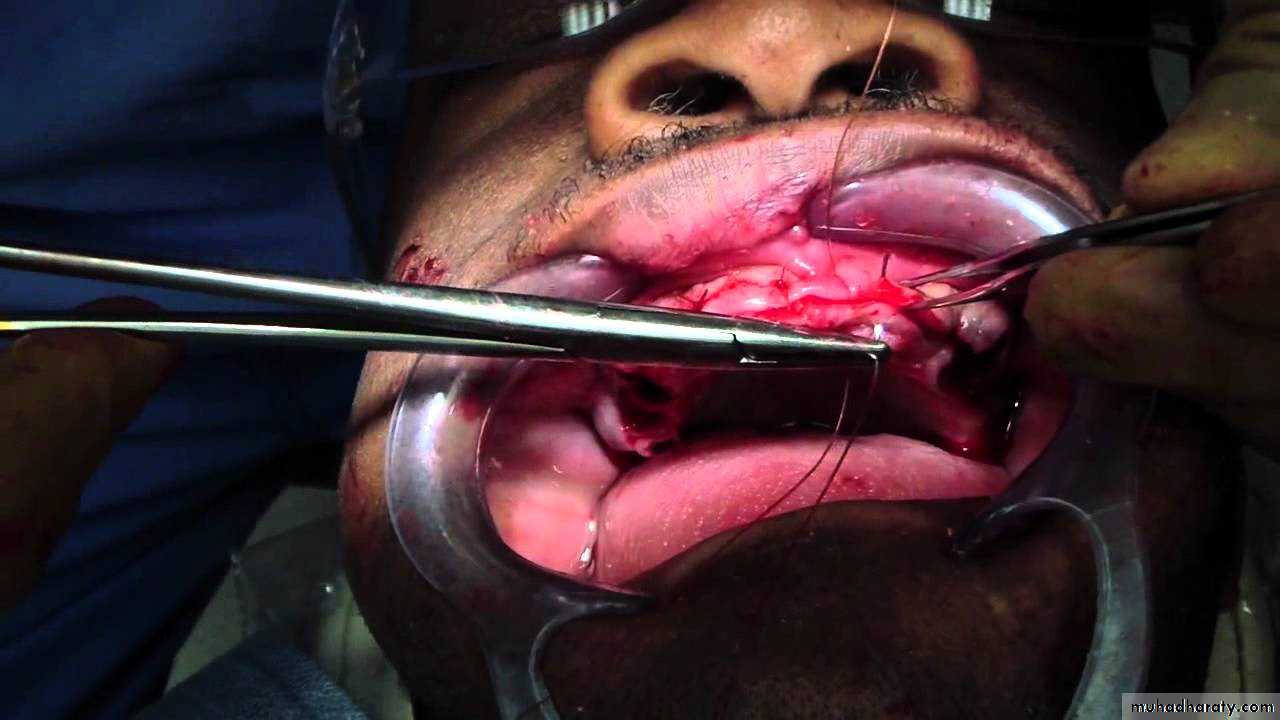

The surgical procedure involves

(1) Extraction of the teeth.(2) Removal of the associated interseptal bone.

(3) Collapse of the labial cortical plate of bone and mucoperiostium, back into the resulting ‘ gutter‘.

18

(4) Insertion of the clear acrylic template to check if bone removal has been sufficient. Blanching of the mucosa is clearly seen beneath the template in any area where there is excessive pressure.

(5) Suturing of the sockets and insertion of the immediate denture.